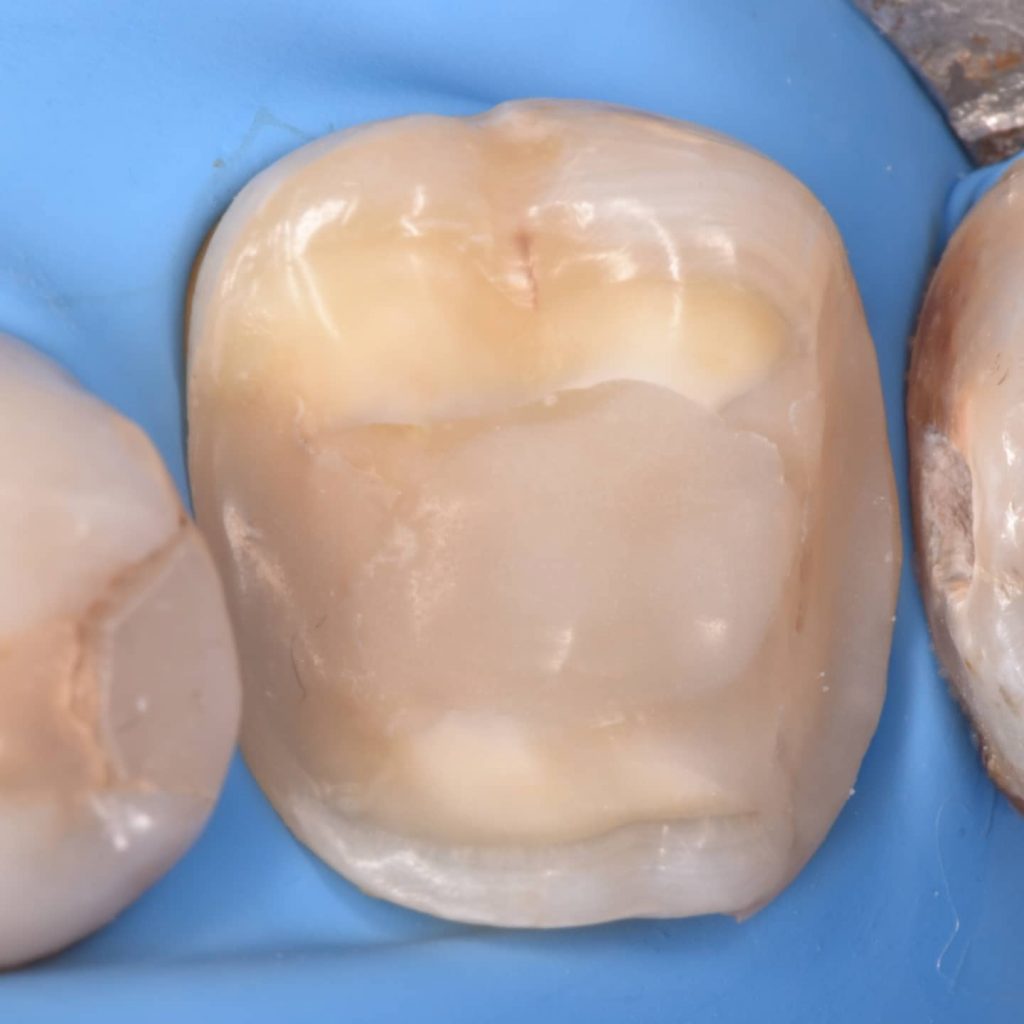

After 6 month of endo treatment the pateint come to complete the final filling as you see the amalgam mesaily should removed

Amalgam removal

Ever x posterior for more support to the filling and for dentin replacement